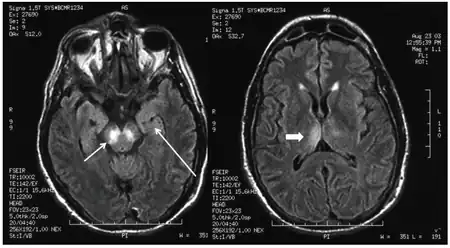

A stroke is an interruption of the blood supply to the brain. Approximately every 40 seconds, someone in the US has a stroke.[7] This can happen when a blood vessel is blocked by a blood clot or when a blood vessel ruptures, causing blood to leak to the brain. If the brain cannot get enough oxygen and blood, brain cells can die, leading to permanent damage.